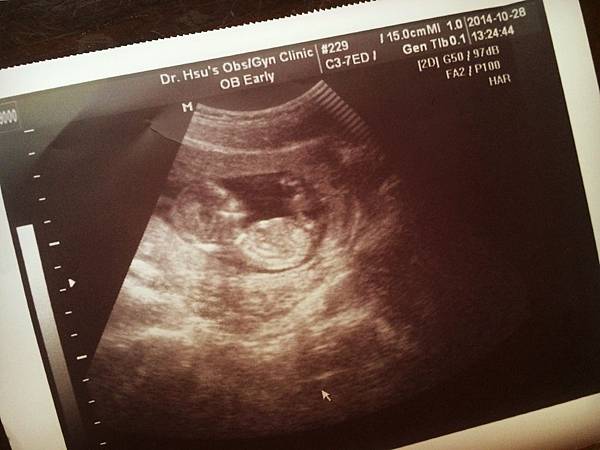

• 【妊娠7w3d~聽到寶寶心跳聲好感動】

八週

今天是第二次例行產檢

對我來說這次好重要

因為要確認寶寶有沒有心跳?